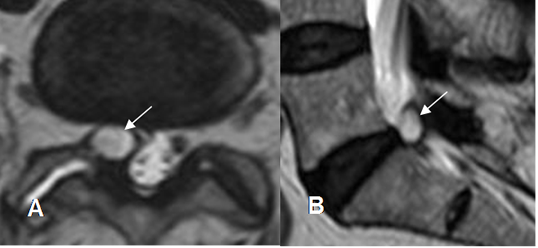

Fig 230. Ruptura de raíces.

A: RM coronal y B: RM axial en STIR. Formación de seudomeningocele izquierdo, por avulsión de las raíces.